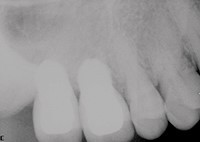

بیمار مردی 32 ساله بود که سابقه پزشکی نامطلوبی داشت. دندان آسیاب اول و دوم (دندان های شماره 2 و 3) حدودا 2 سال قبل به علت پوسیدگی گسترده خارج شد (شکل 1). ریج باقی مانده، اگر چه بسیار گسترده بود (حدود 11 میلی متر)، اما در بعد عمودی به خطر افتاده بود. اسکن های CBCT ارتفاع 5.2 میلی متری لبه ی عقبی را در ناحیه دندان شماره 2 نشان داد (شکل 2). یک ریج آسیب دیده مانند این معمولا با استفاده از روش با روش برداشت تاج سامرز درمان می شود، با استفاده از استئوتوم ها کف سینوس را به اندازه ی 4.0 تا 5.0 میلی متر بالا می کشند تا یک ایمپلنت به طول 8.0 میلی متر را قرار دهند. در محل ایمپلنت شماره 3، کف سینوس شیب رو به بالا دارد که نزدیک دیوار جلویی قرار گرفته است. ارتفاع ريج در اين ناحيه 5.9 تا 6.0 ميلي متر بود.

شکل 1: رادیوگرافی پانورامیک قبل از عمل.

شکل 2. CBCT مقطعی ناحیه بی دندان.

چسب های اضافی خارج شده و با رادیوگرافی تأیید شدند (شکل 20).